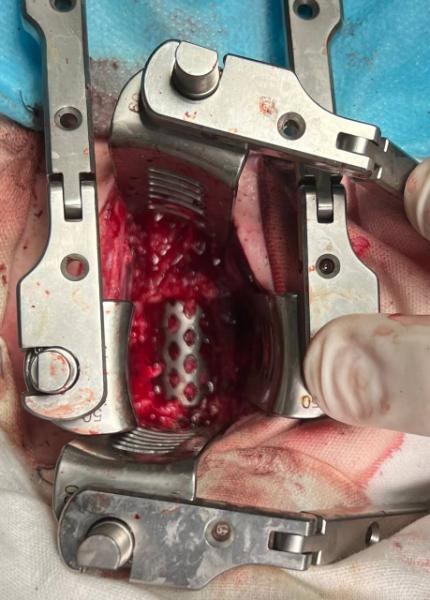

Бригадой нейрохирургов РКБ им. Ш.Ш. Эпендиева в составе Романа Умарова, Алана Лабазанова и Денилбека Исмаилова было решено провести оперативное вмешательство по замещению сломанного участка позвонка титановой пластиной.

Операция по проведению корпоэктомии шейного отдела позвоночника прошла удачно: деформация устранена, а сломанный позвонок заменен протезом. Пациент чувствует себя хорошо и быстро идет на поправку.